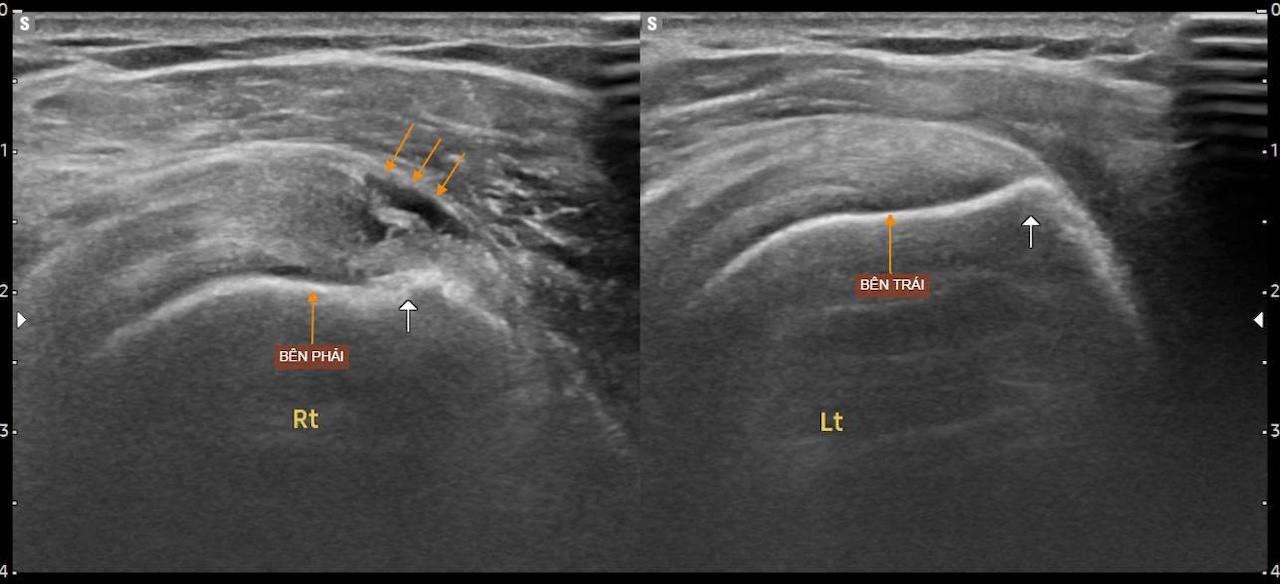

Kết quả siêu âm cho thấy bệnh nhân bị rách bán phần gân cơ trên gai, một trong những gân quan trọng của khớp vai, thường bị tổn thương khi phải thực hiện các động tác đánh bóng lặp lại với cường độ cao.